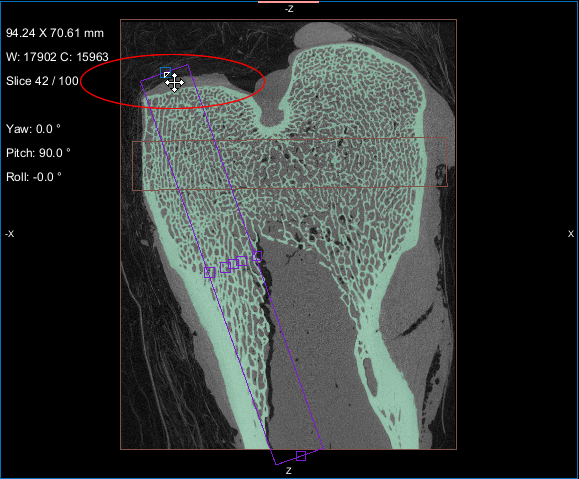

This section of the proximal femur tutorial describes how to compute high-resolution anisotropy maps in different orientations. You should note that when computing high-resolution maps, you should limit the volume of operation to regions that enclose only part of the region of interest. This can be done by creating a series of boxes that describe a particular orientation.

The images below (from left to right) correspond to XZ, XY, and oblique orientations. The computed vector fields are colored by magnitude.

High-definition vector field-based surface anisotropy maps

You can resize and rotate the boxes, as well as change their position within a 2D or 3D view with the control points (see Editing Shapes).

NOTE You can decrease the sampling spacing and radius of influence to 0.0005 m and 0.0015 m, respectively, since you will be computing maps within a sub-volume.